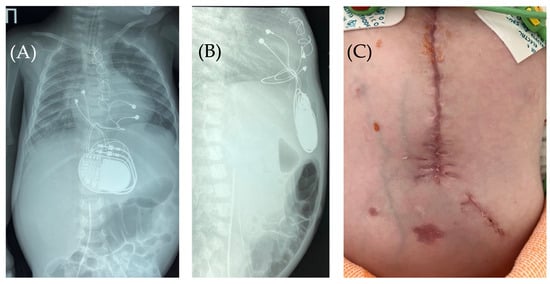

The skin in the area of the abdominal wall soft tissue bulge had normal color and temperature. Palpation revealed soft tissue with no detectable fluctuations. The pacemaker pocket was palpated within its bed. To rule out pneumothorax and perforation of a hollow abdominal organ, chest and abdominal radiography and fluoroscopy were performed, as well as GI contrast imaging (Figure 2 and Figure 3).

Fluoroscopy and chest and abdominal radiography revealed no signs of pneumothorax. A demarcated area of free air was visualized in the upper anterior abdominal wall along the midline, projecting to the pacemaker pocket. The passage of radiocontrast agent through the gastrointestinal tract was observed dynamically and found to be normal. No signs of hollow organ perforation or intestinal obstruction were detected (Figure 2, Figure 3 and Figure 4).

Figure 3. Control of the passage of radiocontrast agent (yellow arrow) through the gastrointestinal tract to exclude perforation of a hollow organ of the abdominal cavity. Frontal (A,C) and lateral (B) view of the chest X-ray 1 h (A,B) and 2.5 h (C) after radiocontrast agent administration. R: right side; L: left side.

Figure 4. Chest X-ray examination—frontal (A) and lateral (B) view. Chest X-ray shows no pneumothorax, but pneumopericardium, pneumomediastinum with air are present at the pacemaker pocket site (red arrow). Radiocontrast agent (yellow arrow) at the gastrointestinal tract.